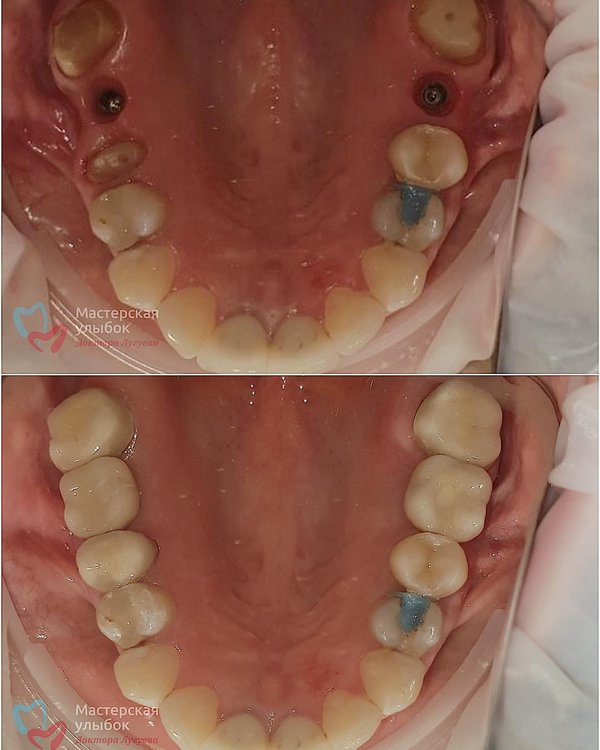

Установка металлокерамических коронок на имплантах OSSTEM. Работа врача: Лугуева Арслана